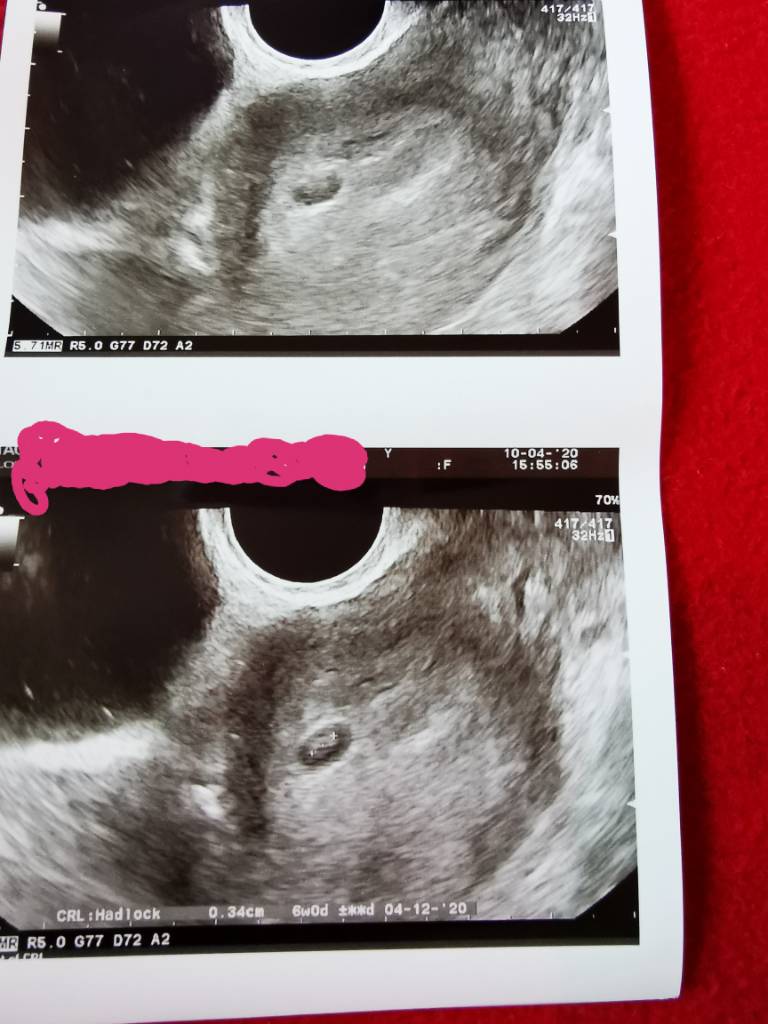

Ale dziękuję Ci bardzo za i formacje. U mnie w 6 tyg usg...

A jak byłam w 5+ 3 to jeszcze nie biło a później byłam w 8 tygodniu i biło normalnie [emoji4]

IMG_20200410_173255.jpeg